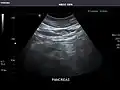

Renal ultrasonography

Ultrasonography of the kidneys is essential in the diagnosis and management of kidney-related diseases. The kidneys are easily examined, and most pathological changes in the kidneys are distinguishable with ultrasound.[7]